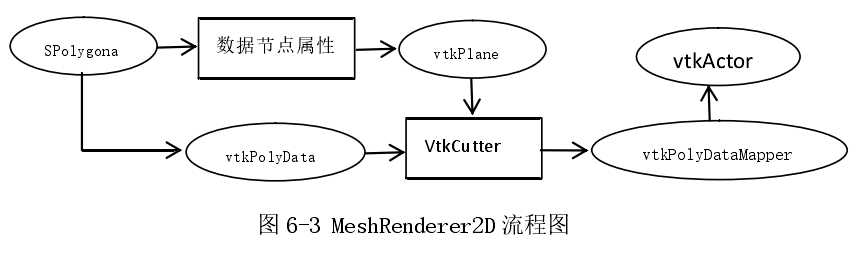

MeshRenderer2D 类主要功能是将三维多边形 SPolygonal 数据绘制到二维视图上。其配置流程如下图(图 6-3)所示:

其中,VtkCutter 的作用是从 vtkPolyData 获取 vtkPlane 对应的图像数据。